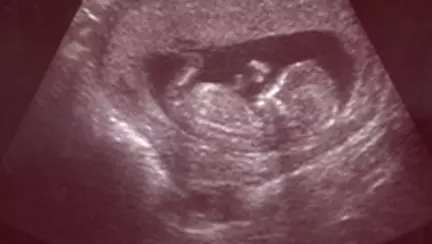

In mod obisnuit, placenta se detaseaza de peretele uterului dupa nastere. In unele cazuri insa, placenta se detaseaza de uter prea devreme, iar aceasta afectiune e cunoscuta ca placenta abruptio. Desi nu este frecvent intalnita, placenta abruptio este extrem de periculoasa, atat pentru mama, cat si pentru bebelus. Care sunt simptomele de placenta abruptio Principalul

Placenta abruptio reprezinta separarea prematura a placentei de uter inainte de nastere.